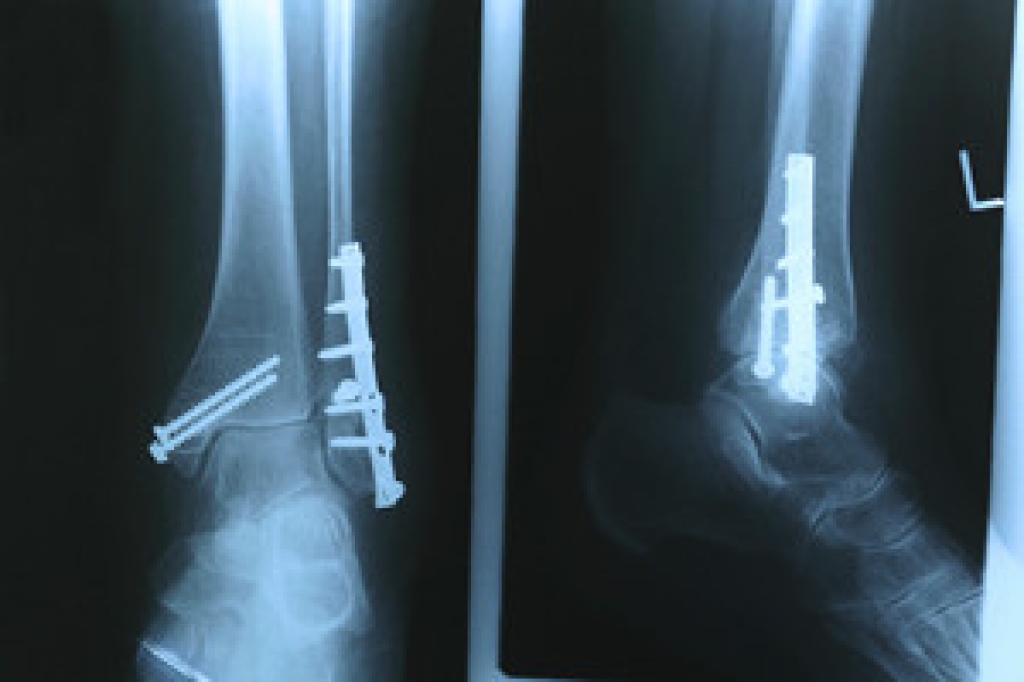

To figure out the cause of foot pain, podiatrists utilize several different methods. This can range from simple visual inspections and sensation tests to X-rays and MRI scans. Prior medical history, family medical history, and any recent physical traumatic events will all be taken into consideration for a proper diagnosis.

Treatment depends upon the cause of the foot pain. Whether it is resting, staying off the foot, or having surgery; podiatrists have a number of treatment options available for foot pain.